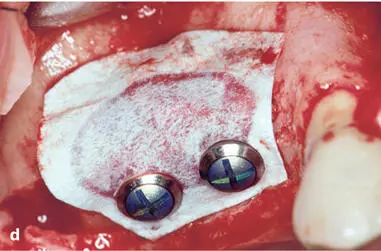

Early on, several complications were observed with both approaches, and modifications of the surgical techniques were proposed to improve the predictability of successful treatment outcomes. One frequent complication was the collapse of the ePTFE membranes, which reduced the volume of the regenerated tissue underneath the membrane. In addition, some of the regenerated sites demonstrated insufficient bone formation and the formation of a periosteum-like tissue underneath the membrane. 37 , 40 Therefore, bone fillers such as autografts or allografts were recommended by various groups, primarily to support the membrane and reduce the risk of membrane collapse. 54 – 56 The combination of ePTFE membranes and autogenous bone grafts provided good clinical outcomes for both approaches. Some of these patients are still being followed and documented up to 25 years after surgery (Figs 1-2 to 1-4).